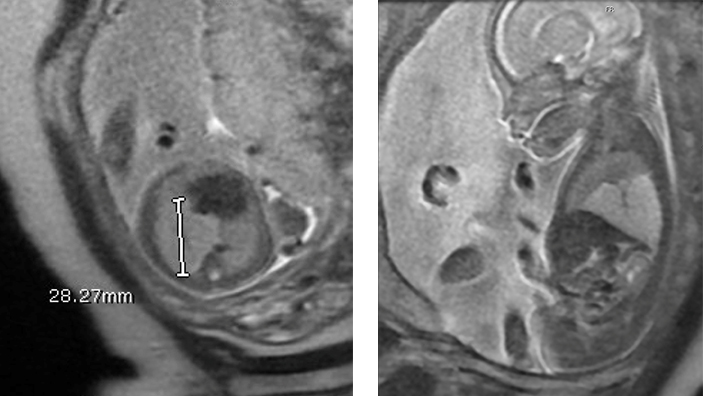

Fetal MRI is a valuable adjunct to ultrasound in the evaluation of CPAMs. It is often not possible to determine which lobe is involved in the CPAM by ultrasound. In contrast, fetal MRI is often able to delineate the T2 signal intense CPAM from compressed normal lobes which have a lower T2 signal compared to normal lungs. Fetal MRI has proven useful when the diagnosis based on ultrasound alone is uncertain and increases the specificity of the diagnosis (51-53).

Macrocysts within CPAMs are highly signal intense of T2 weighted images with adjacent solid components of the CPAM also being high on T2-weighted images. CPAMs that are entirely macrocystic are hyperintense on T2. Microcystic CPAMs may be difficult to distinguish from lobar or segmental hyperinflated lung. The presence of cysts confirms the diagnosis of CPAM, but in the absence of macrocysts, it may be difficult to distinguish a hyperinflated lung from a type III CPAM. The vascular distribution in a hyperinflated lobe or segment is normal, whereas in a CPAM, the normal vascular distribution is disrupted by irregular spacing of vessels by signal intense parenchyma. It may not be possible to distinguish microcystic or type III CPAMs from hyperinflation on prenatal MRI and postnatal thin-section CT scans with intravenous contrast may be needed to make this distinction with certainty. It may also be difficult to distinguish a microcystic hybrid CPAM with a systemic arterial feeding vessel from an intralobar bronchopulmonary sequestration. Both BPS and a type III CPAM appear homogeneously signal intense on T2 weighted images and both will have a flow void from the systemic feeding vessel. A concomitant pulmonary arterial feeding vessel can be seen in hybrid CPAMs as well as intralobar BPS.

There have been several MRI-derived quantitative measurements reported to predict the risk of developing hydrops and postnatal respiratory compromise. MRI-specific quantitative measurements include the fetal MRI-derived lung mass volume ratio (LMVR) (which is the MRI equivalent of the CVR), the lesion-to-lung volume ratio (LLV), and the observed/expected normal fetal lung volume (O/E-NFLV) (55). Of these MRI-derived measurements, the LMVR was found to be the strongest predictor of the development of hydrops and neonatal respiratory distress after delivery. But there was no direct comparison made between LMVR and CVR. While LMVR is measured by the sum of serial coronal MRI images, CVR is measured by 3-dimensional measurements obtained by ultrasound and normalized for gestational age by dividing by the head circumference. One would predict that LMVR would be equivalent to CVR as they are measuring the same thing using different modalities.